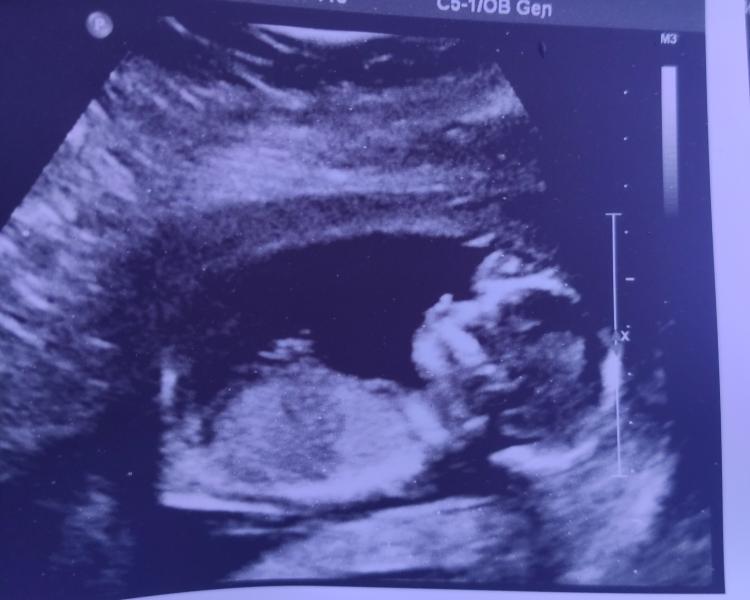

Всем приветы 🧚. Были на УЗИ, все хорошо. Пол не сказали (

Вроде девочка у вас)

Почему мне кажется, что мальчик? 😄 Хотя, конечно , я вообще в этом не спец 😄